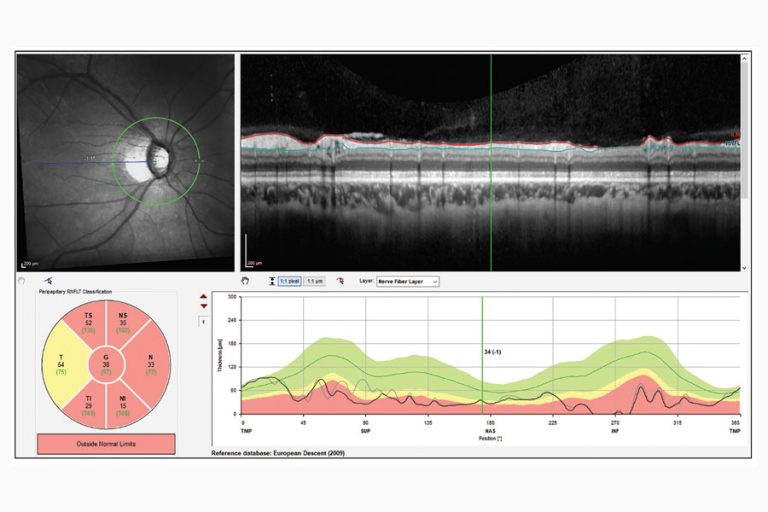

“El otro ejemplo es que si el espesor del sector es bajo, es porque hay picos retinianos desplazados de la capa de fibras nerviosas debido a la miopía; entonces, esos sectores pueden clasificarse como anormales o ‘rojos’”, continúa el Dr. Asrani. “Por lo tanto, no queremos guiarnos solo por las indicaciones en color del informe. Tenemos que ver el panorama completo mirando los escaneos y la segmentación, para que podamos identificar correctamente si se trata de glaucoma o no”.

En lugar de evaluar los indicadores en los colores rojo, verde y amarillo, hay una solución más sencilla para diagnosticar el glaucoma. “Es extremadamente raro que el glaucoma sea simétrico, excepto cuando ambos ojos están en etapa terminal, porque la asimetría es el sello distintivo del glaucoma”, dice el Dr. Asrani. “Si el médico observa el diagrama de simetría, o el gráfico de simetría, puede ajustar las dos imágenes una al lado de la otra y ver si hay alguna simetría: esa es una de las formas más fáciles de diagnosticar el glaucoma”.

Tenga en cuenta los datos que faltan en el mapa de desviación de la OCT. “La falta de datos es común porque si el ojo no está correctamente centrado, no podrá escanear toda el área”, dice la Dra. Shen. “Si los datos que faltan están dentro del círculo de escaneo, por lo general el técnico escaneará al paciente nuevamente; sin embargo, si los datos que faltan están fuera del círculo de escaneo, a menudo, el técnico pasará al siguiente paciente para obtener imágenes”. (Figura 1)

Los mapas de desviación pueden contener artefactos que pasan desapercibidos al observar las imágenes raw. Los artefactos de movimiento son un ejemplo común. “Estos son sutiles y un poco más difíciles de detectar porque no se ven en este formato de imagen”, dice el Dr. Shen. «Si observamos la imagen raw, la vemos bella y suave. Si vemos el mapa de desviación y observamos líneas horizontales dentro del círculo de escaneo, entonces se registran como un adelgazamiento en la capa de fibra nerviosa. Desafortunadamente, es difícil verlo utilizando únicamente el análisis de progresión; la mejor manera de observar los artefactos de movimiento es con el mapa de desviación”. (Figura 2)